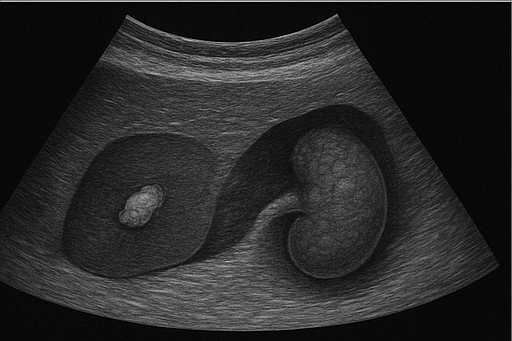

- 신장 결석: 신장에 생긴 돌로, 초음파에서 밝은 음영과 그림자로 나타납니다.

- 신장 종양: 신장에 발생하는 종양으로, 크기와 모양의 변화를 통해 의심할 수 있습니다.

- 비장 비대: 비장이 정상보다 커진 상태로, 초음파를 통해 크기를 측정하여 확인할 수 있습니다.